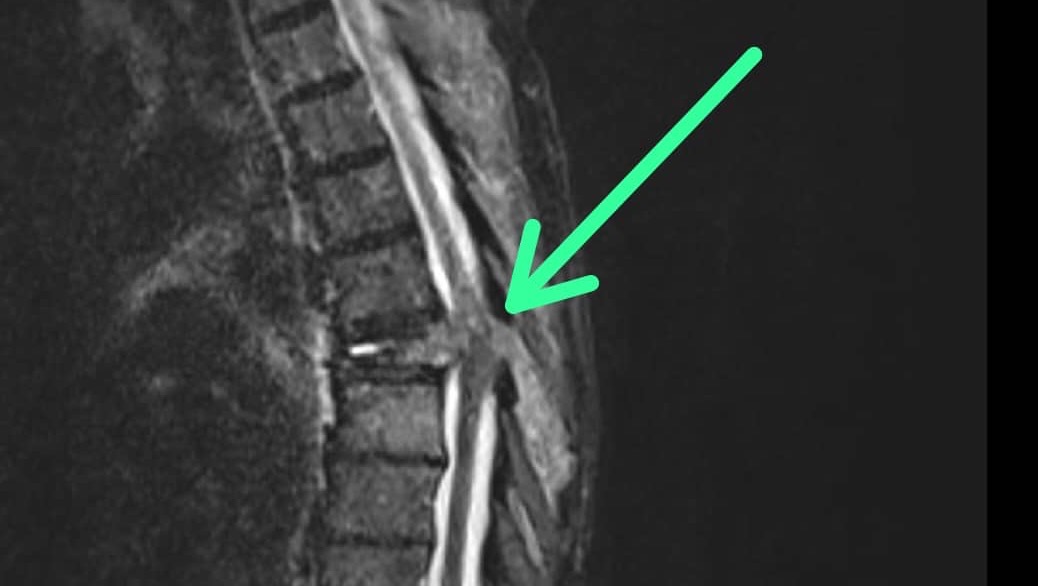

Hace poco nos dieron una noticia muy dura: mi papá tiene un tumor metastásico que comenzó en el riñón y se extendió a la columna. Como consecuencia, sufrió una fractura que requiere una cirugía urgente: una laminectomía descompresiva en los niveles T6-T7-T8. Esta operación es vital para aliviar el dolor, evitar complicaciones mayores y darle una mejor calidad de vida ❤️.

Recently, we received heartbreaking news: my dad has a metastatic tumor that started in his kidney and spread to his spine. As a result, he suffered a fracture that requires urgent surgery: a decompressive laminectomy at T6-T7-T8.

This surgery is vital to relieve his pain, prevent further complications, and give him a better quality of life. Unfortunately, the cost of the operation and hospitalization is far beyond our family’s means.